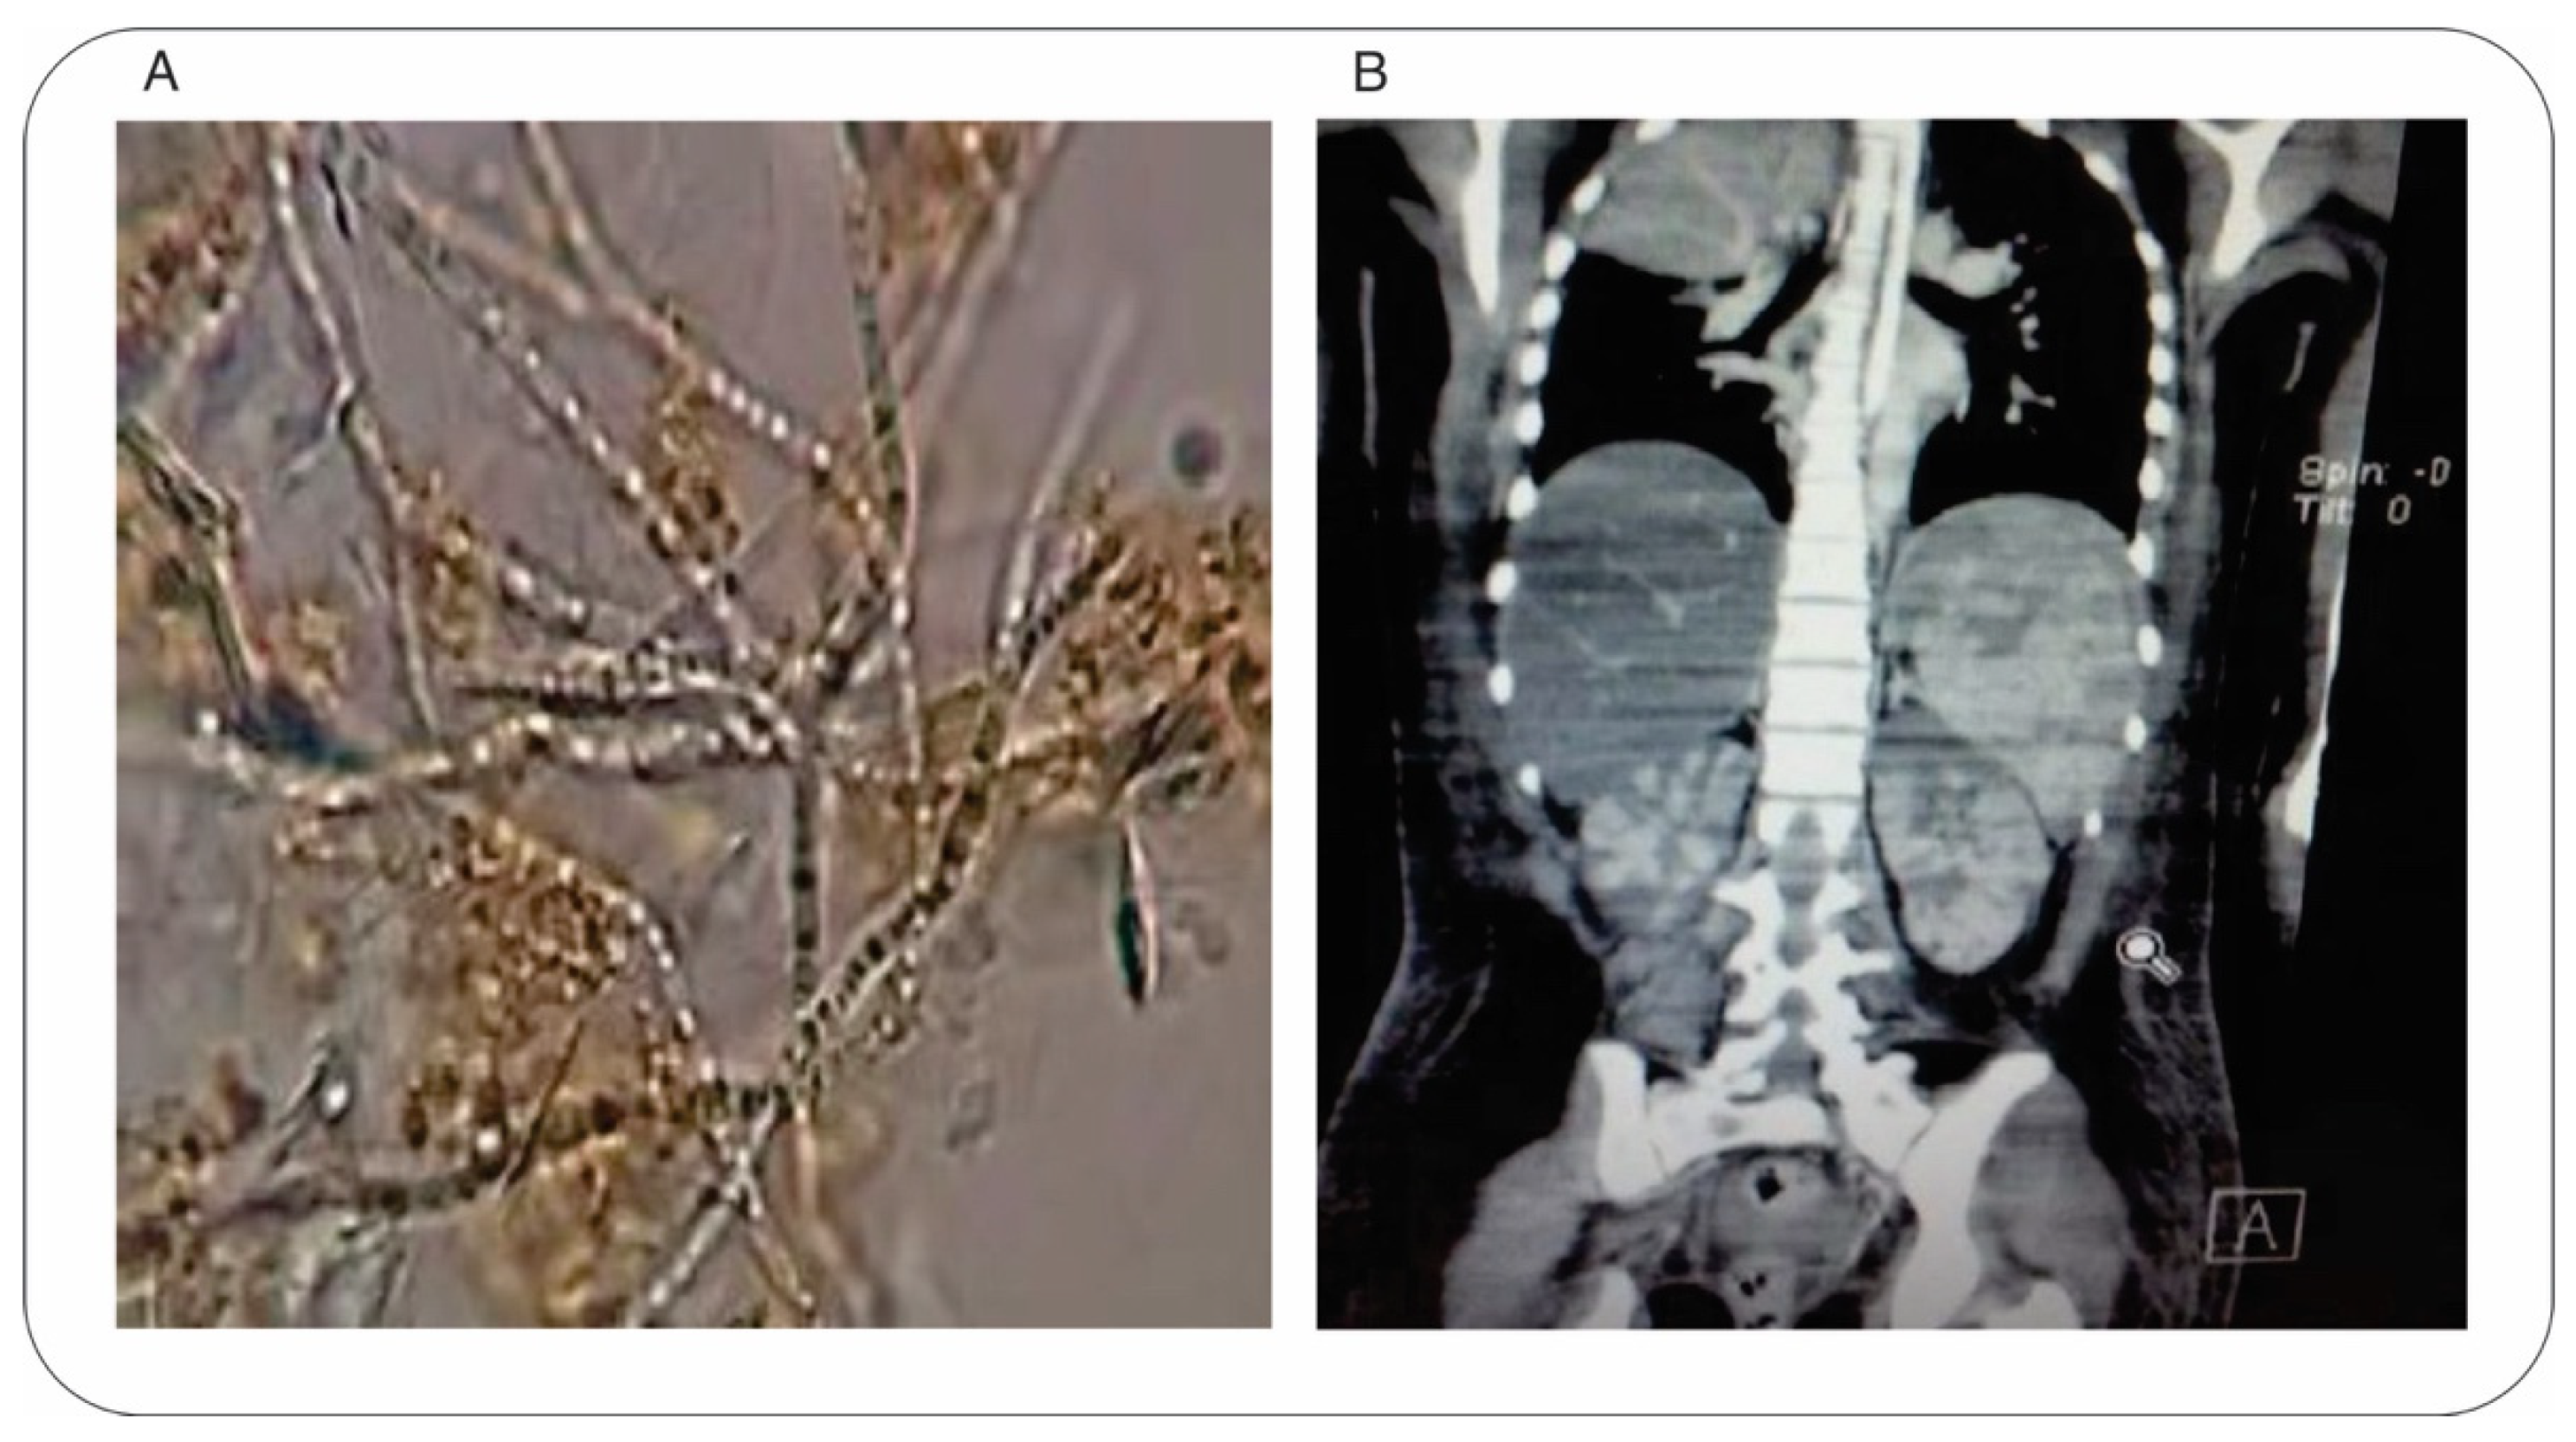

2. Case Presentation